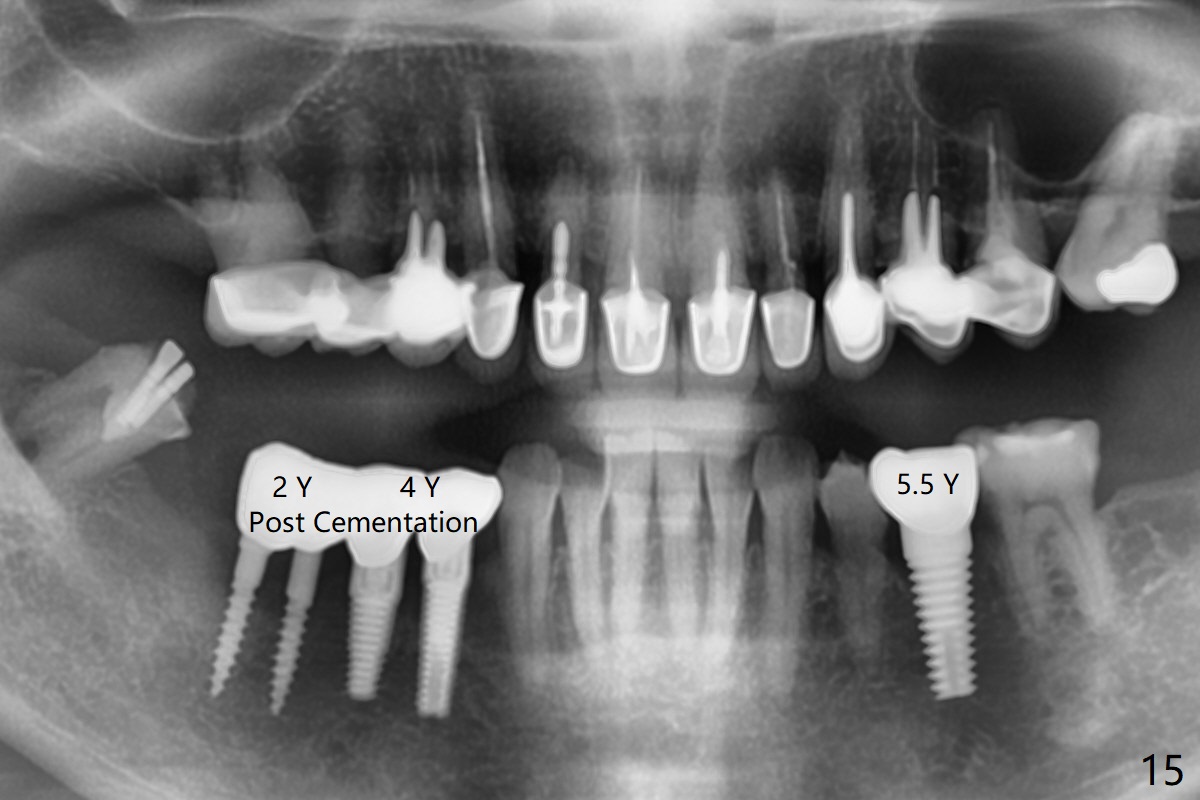

Two of 2.5 mm 1-Piece Implants M

The edentulous ridge at #30 is narrow (Fig.1). After ridge reduction, osteotomy is initiated with 1.2 mm drill for 10 mm; the mesial osteotomy is to be changed (Fig.2 red line). Using a 1.2 mm drill placed in the distal osteotomy (Fig.3 D), the mesial osteotomy changes in trajectory with subsequent placement of a 2.5x10(4) mm 1-piece implant. Since the mesial implant is high in occlusion, the cuff of the distal implant is changed to be 2 mm (Fig.4 (shorter black line)). Panoramic X-ray is taken to show no violation of the Inferior Alveolar Canal (Fig.5 red dashed line). These two 1-piece implants are slightly lingually placed (Fig.6). The crestal bone around the implants resorbs without thread exposure 5 months postop (Fig.7). Impression is taken for a splinted crown (Fig.8-12). There is no metal show around the 2.5 mm 1-piece implants 6 months postop (advantage) vs. that at #28 and 29 (Fig.13). Bitewing is taken post cementation to determine whether residual cement is present (Fig.14). There is periodic swelling and pain in the lower right quadrant 2 years post cementation (Fig.15). In fact periimplantitis appears to have developed at #28 (Fig.16) with loss of the buccal bone (Fig.17,18). The buccal bone loss is less at #29 (Fig.19) and #20 (Fig.23) and no at #30 mesial and distal implants (Fig.20,21). A much smaller implant will be placed lingually at #28 immediate (Fig.24,25).